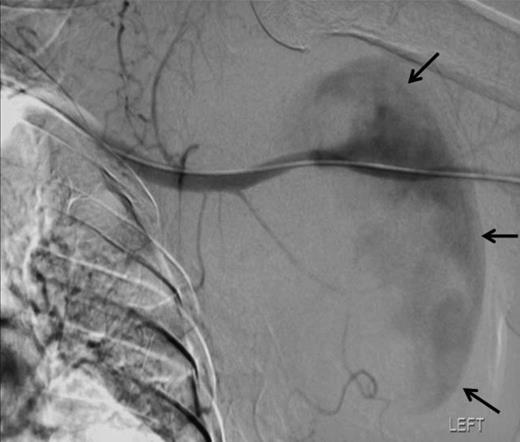

Angiographic localisation of the lesion in the third part of the axillary artery. Please note extravasation of contrast into the sac (arrows)

Ten weeks later a repeat orthopaedic review was requested by the rehabilitation team. There had been a slow onset and progression of oedema in the arm, with gradual progression of neurological deficit to the point at which the arm became useless and insensate. An increase in axillary bruising was noted. Also, the patient required a three-unit blood transfusion for a drop in haemoglobin six weeks after the injury. There was a thrill over the whole pectoral region and signs of venous hypertension in the arm. The left radial, ulnar and brachial pulses were normal. Repeat X ray showed subluxation of the left shoulder joint (figure 2). CT angiography revealed a distal axillary pseudoaneurysm with a sac of 15cm diameter (figure 3).